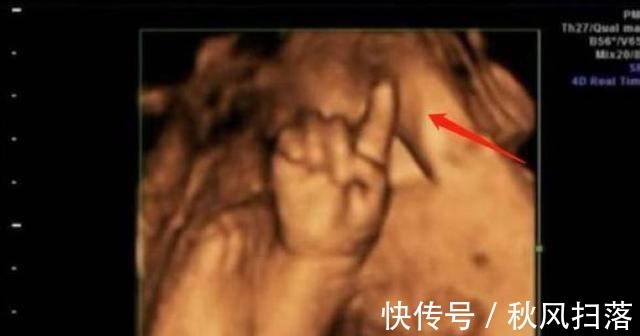

第一次做检查时,胎儿的脸部、身体都看得非常的清楚,让陈女士感到了很大的安慰。值得一提的是,孩子的一只手伸出了一个手指,非常的可爱。让人没想到的是,第二次检查时,孩子的手指伸出了两根,第三次手指变为了三根,最后一次检查,孩子的手指就变成了四根。

医生看到这种情况,也是非常的吃惊,他还调侃道:这孩子可是北大清华的料,可不能耽误人家,陈女士听后非常的开心。就这样,\\\"天才胎儿\\\"在网上迅速火了起来,他在子宫中掰手指算数成为了网友们新奇的谈资。